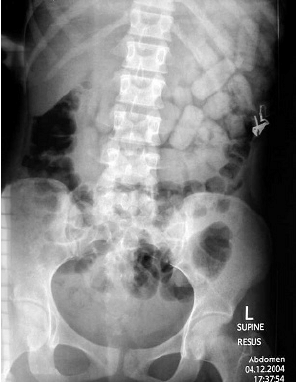

해외 여행을 마치고 돌아온 28세 남성이 마약 밀수 혐의로 공항에서 체포되어 병원으로 이송되었다. 복부 X선 촬영 결과가 첨부되어 있다. 이 환자에게 적절한 치료 방법은 무엇인가?

• X-ray상 약봉지로 추정되는 음영이 복부에 다수 관찰되므로 마약 밀반입을 위해 약봉지를 삼켰을 것으로 추정된다.

• 약물이 위장관 내로 유출될 경우 매우 심각한 drug intoxication 증상이 나타날 수 있으므로 whole bowel irrigation을 통해 이를 배출하도록 해야 한다.